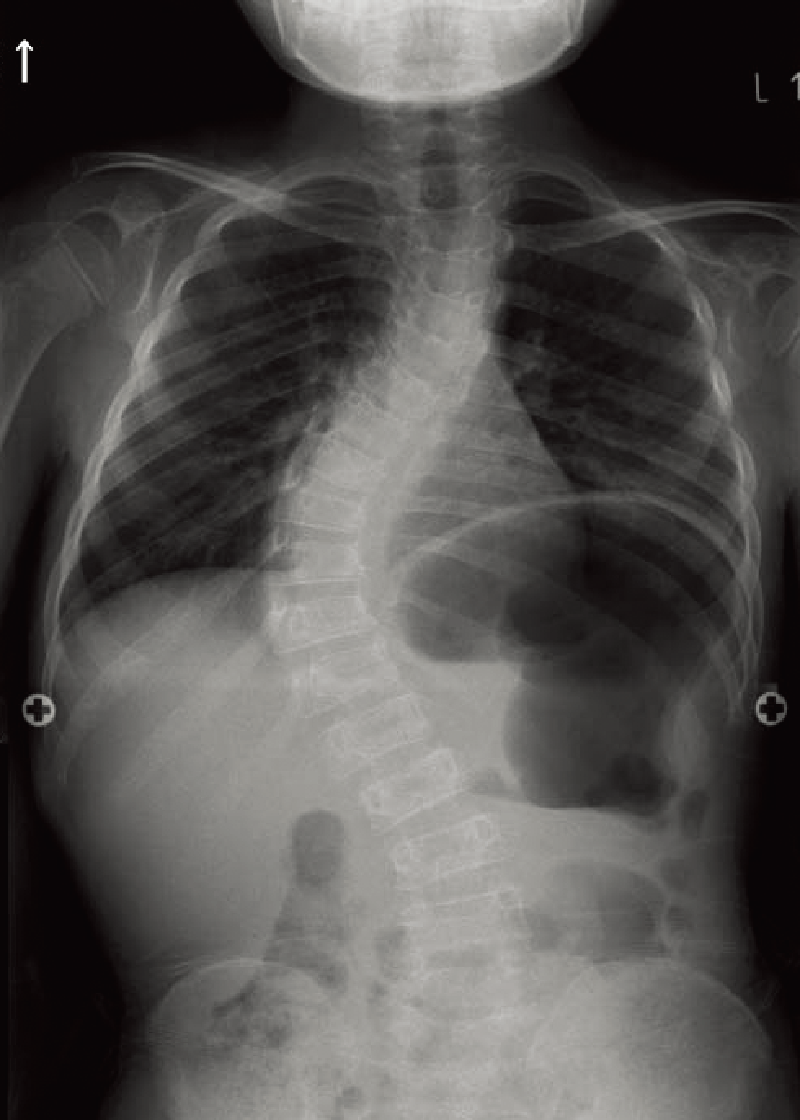

A. 背面像(6歳、女):内反膝を伴った体幹短縮型低身長。

B. 両下肢正面像(6歳、女):著明な内反膝および、大腿骨頭骨端核や膝周囲の骨端核の骨化遅延を認める。